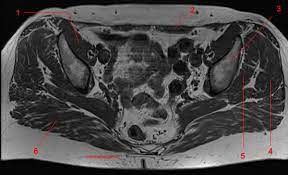

Posted by kenneth on november 18, 2019. Mri is the modality of choice in assessing the complex perineal lesions and their relations to the adjacent structures. 6.1a, b) is a bony ring consisting of paired innominate bones, the sacrum and coccyx. Anatomically, the pelvis can be divided into true and false pelvis by an oblique line that extends from the sacral promontory along the anterior aspect of s1 to the symphysis pubis. Pelvic muscle anatomy chart, pelvic muscle anatomy male, pelvic muscle anatomy pdf, pelvic muscles anatomy axial, pelvic muscular anatomy ct, human muscles, pelvic muscle anatomy chart, pelvic muscle anatomy male, pelvic muscle anatomy pdf, pelvic muscles anatomy axial, pelvic muscular anatomy ct. Magnetic resonance imaging (mri) devices can provide direct transverse, sagittal, and coronal plane images. If these muscular tissues end up being weak. Wasnik, mbbs, mda, michael b. Use the mouse scroll wheel to move the images up and down alternatively use the tiny arrows (>>) on both side of the image to move the images.>>) on both side of the image to move the images. Mri anatomy images of the abdomen. Dotted line in a ) show the anatomy of the. The innominate bones articulate with each other anteriorly and with the sacrum posteriorly. The majority of the time, these muscular tissues are quite solid and also are able to support the pelvic bone.

This mri male pelvis axial cross sectional anatomy tool is absolutely free to use. Use the mouse scroll wheel to move the images up and down alternatively use the tiny arrows (>>) on both side of the image to move the images.>>) on both side of the image to move the images. Anteriorly, pubocervical fibromuscularis is attached to the levator ani using arcus tendineus fascia pelvis (fig. The majority of the time, these muscular tissues are quite solid and also are able to support the pelvic bone. Anatomically, the pelvis can be divided into true and false pelvis by an oblique line that extends from the sacral promontory along the anterior aspect of s1 to the symphysis pubis. Pelvic bones are held together by the two main joints of the pelvis; This mri hip joint axial cross sectional anatomy tool is absolutely free to use. The pelvic cavity opens superiorly to, and is continuous with, the abdominal cavity through the pelvic inlet. 1 the greater, or false, pelvis is situated above this plane. E anatomy is an award winning interactive atlas of human anatomy. In this image, you will find ascending colon, appendix, psoas muscle, ureter, gluteus minimus, lumbosacral trunk, gluteus medius, gluteus maximus, sacroiliac joint, the lateral sacral crest in it. This is since pelvic muscular tissues are generally one of the major weak points in a lady's body. Key facts about the muscles of the pelvic floor.

Conclusions • the primary imaging modalities for the abdomen and pelvis are plain film, ultrasound, and ct. Anteriorly, pubocervical fibromuscularis is attached to the levator ani using arcus tendineus fascia pelvis (fig. The pubic symphysis and the sacroiliac joint, and reinforced by pelvic muscles. Wasnik, mbbs, mda, michael b. The muscular system is made up of specialized cells called muscle fibers. Pelvic wall muscles include the anterior and inferior obturator internus, and the posterior iliacus, piriformis, and psoas major (figures 8 and 9). Use the mouse scroll wheel to move the images up and down alternatively use the tiny arrows (>>) on both side of the image to move the images.>>) on both side of the image to move the images. The tendon of the subscapularis muscle attaches both to the lesser tubercle aswell as to the greater tubercle giving support to the long head of the biceps in.

A pelvis mri (magnetic resonance imaging) scan is an imaging test that uses a machine with powerful magnets and radio waves to create pictures of the single mri images are called slices. The pubic symphysis and the sacroiliac joint, and reinforced by pelvic muscles. The bony framework of the pelvis is called the pelvic girdle.it is composed of the two hip bones and the sacrum. E anatomy is an award winning interactive atlas of human anatomy. Conclusions • the primary imaging modalities for the abdomen and pelvis are plain film, ultrasound, and ct. This mri pelvis cross sectional anatomy tool is absolutely free to use. Pelvic bones are held together by the two main joints of the pelvis; This mri hip joint axial cross sectional anatomy tool is absolutely free to use. Mri is the modality of choice in assessing the complex perineal lesions and their relations to the adjacent structures. 12 photos of the pelvic muscle anatomy mri. They form a large sheet of skeletal muscle that is thicker in some areas than in others. Although ultrasound is frequently indicated for the primary evaluation of Anatomically, the pelvis can be divided into true and false pelvis by an oblique line that extends from the sacral promontory along the anterior aspect of s1 to the symphysis pubis.